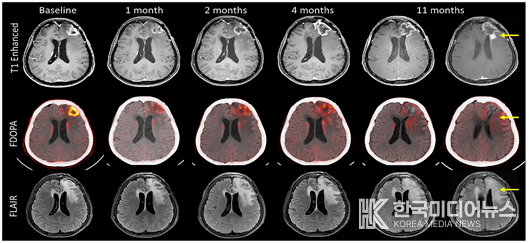

특히 일부 환자에서 치료 수개월 후 방사선 괴사가 의심되는 영상 소견이 관찰됐으나, 이는 실제 종양 진행이 아닌 위양성 진행(pseudoprogression) 가능성이 높았으며, 항혈관신생제 치료 후 증상이 호전됐다. 이는 BNCT 치료 이후 영상 판독과 임상 판단에 있어 고도의 전문성이 필요함을 시사한다.